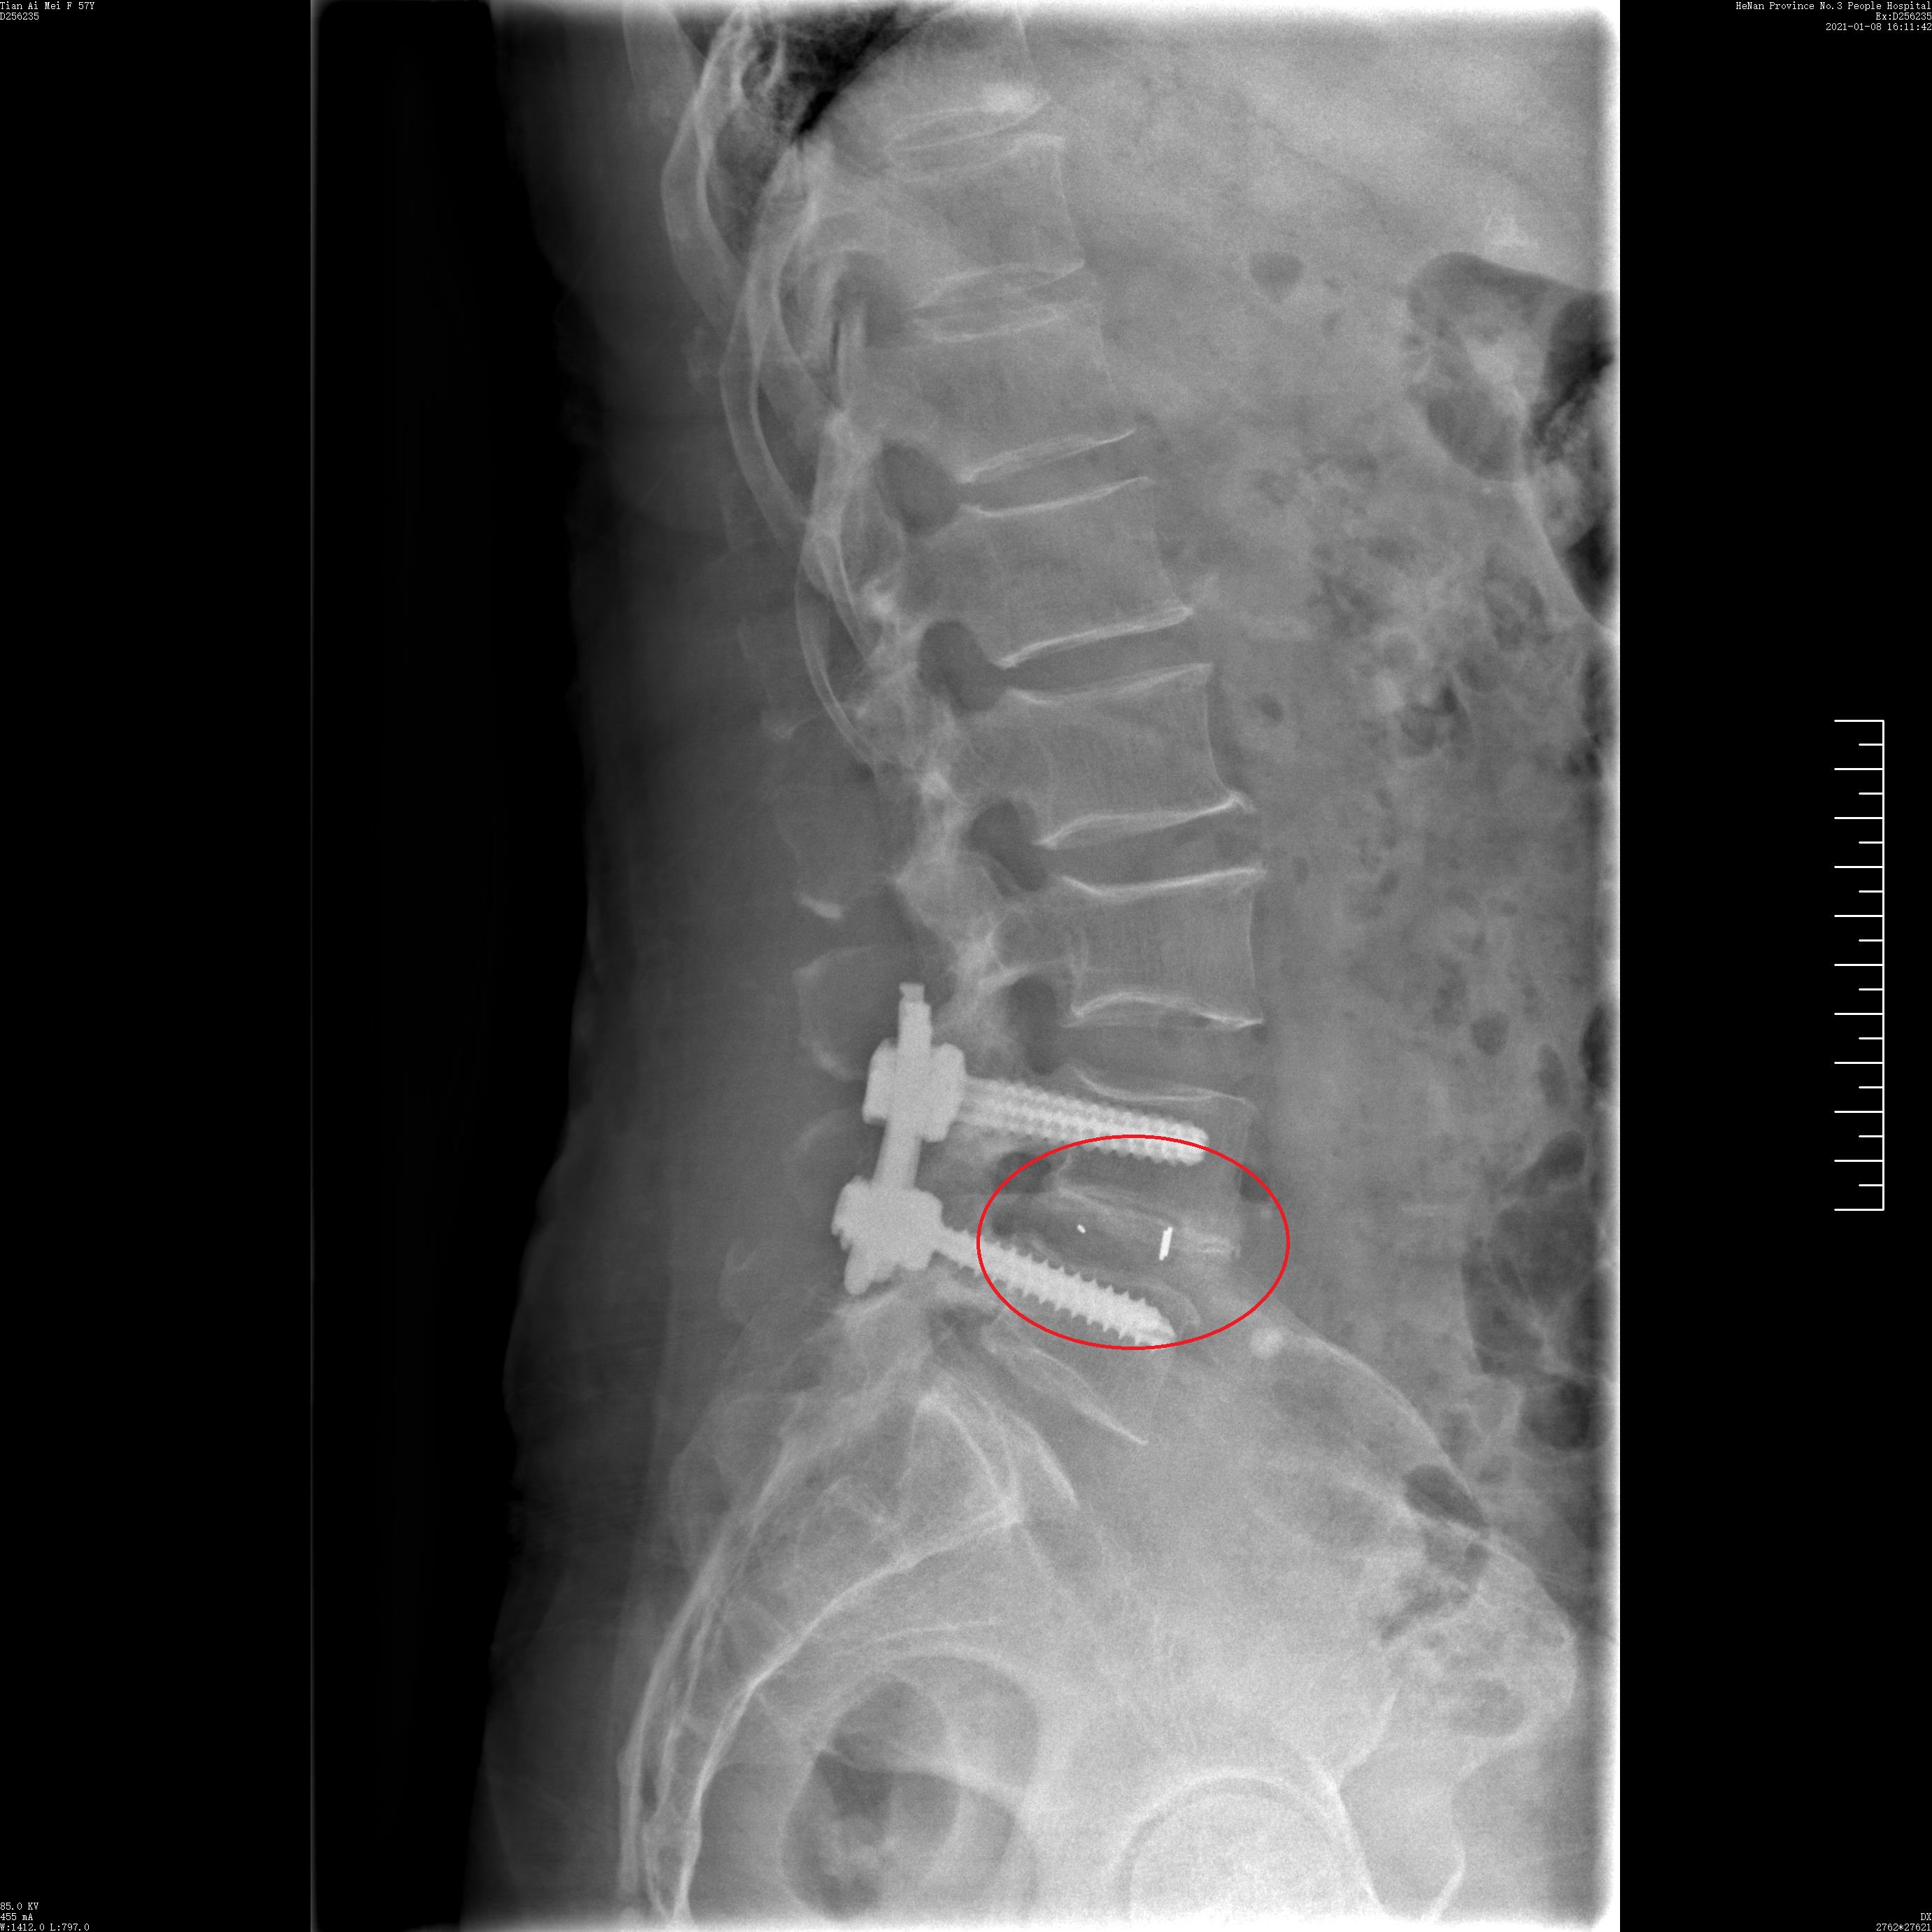

患者,女,57岁,2年前出现活动后腰部疼痛,保守治疗后稍缓解,1年前开始出现左臀部酸困不适,半个月前出现腰部及左髋部疼痛明显加重,伴左下肢麻木不适,为求进一步治疗来到我院椎间盘中心。

入院后,完善相关检查,诊断为腰椎滑脱症(L4/5),予以实施了全麻下UBE技术L4/5镜下融合滑脱复位内固定术。

术前侧位片

术后侧位片